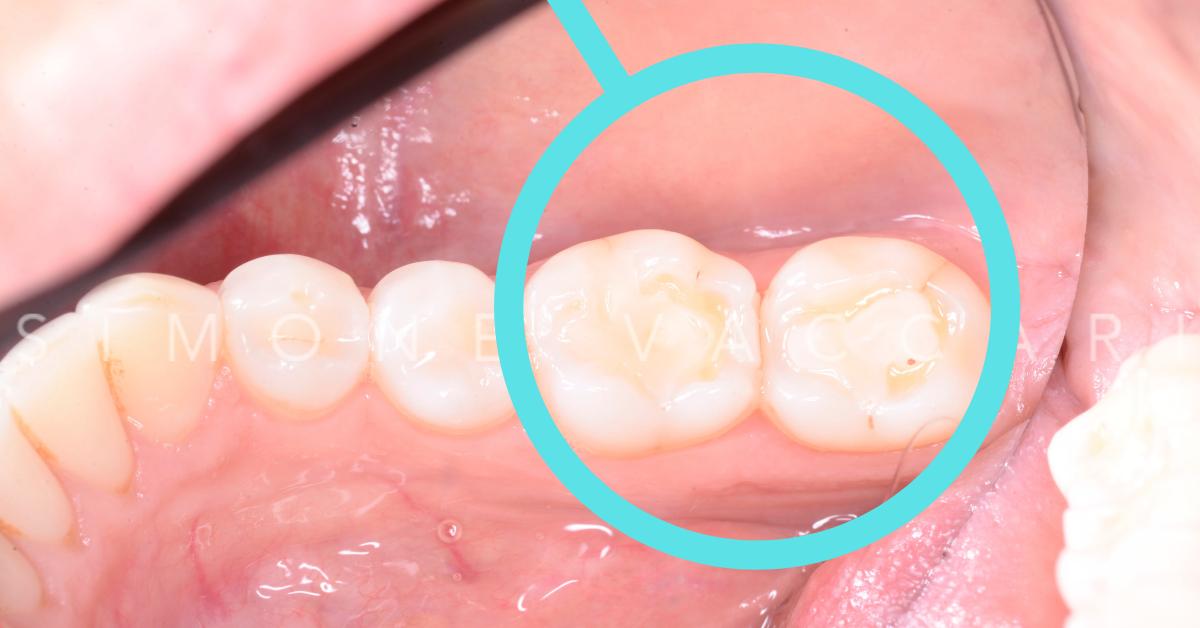

Sui due molari è presente una otturazione bianca e attorno appara ampia area di erosione

Stesso fenomeno "Restoration standing proud" da altra angolazione